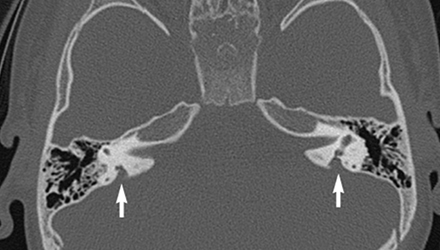

SLC26A4基因--大前庭導(dǎo)水管相關(guān)致聾基因

SLC26A4基因定位于人類染色體7q31,SLC26A4基因和大前庭導(dǎo)水管綜合征相關(guān)突變位點的發(fā)現(xiàn),證實SLC26A4是大前庭導(dǎo)水管綜合征的責(zé)任基因。

我們平時提到的“一巴掌打聾”、“一跤摔聾”其實都與SLC26A4基因突變有關(guān),絕大多數(shù)大前庭導(dǎo)水管綜合征都是SLC26A4基因突變?nèi)堑牡湣?/p>

SLC26A4基因編碼一種叫“Pendrin”的跨膜轉(zhuǎn)運蛋白,在機(jī)體離子成分平衡的維持中發(fā)揮重要作用。

在內(nèi)耳,Pendrin表達(dá)于內(nèi)淋巴管、內(nèi)淋巴囊、橢圓囊、球囊等處,異變的蛋白將對這些結(jié)構(gòu)的正常生理功能產(chǎn)生影響,引發(fā)聽損。

SLC26A4基因突變導(dǎo)致的大前庭導(dǎo)水管綜合征的典型表現(xiàn)為兒童時期的聽力損失,90%的患者為雙側(cè)性,聽力損失程度不一,可表現(xiàn)為接近正常或重-極重度。

病程可為穩(wěn)定性、進(jìn)行性或波動性,聽力可逐步下降至全聾;跌倒、撞擊等行為或無外界影響都可能引發(fā)聽力的下降。